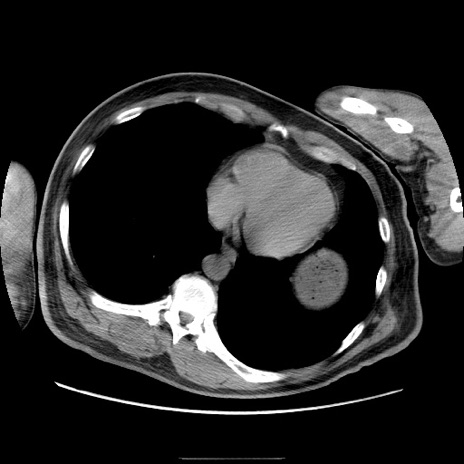

冠状断像

【症例】50歳代男性

【主訴】腹痛

【現病歴】AVMからの被殻出血のため回復期リハ病棟入院中。 本日午後3時頃急に下腹部痛が出現した。

【既往歴】AVM、被殻出血、虫垂炎、高血圧

【身体所見】意識晴明、左半身不全麻痺、会話の理解は良好、36.5°C、腹部:膨隆、全体に板状硬、下腹部正中に圧痛点あり、反跳痛-、筋性防御不明、右下腹部にope scar

【データ】WBC 9400、CRP 0.06